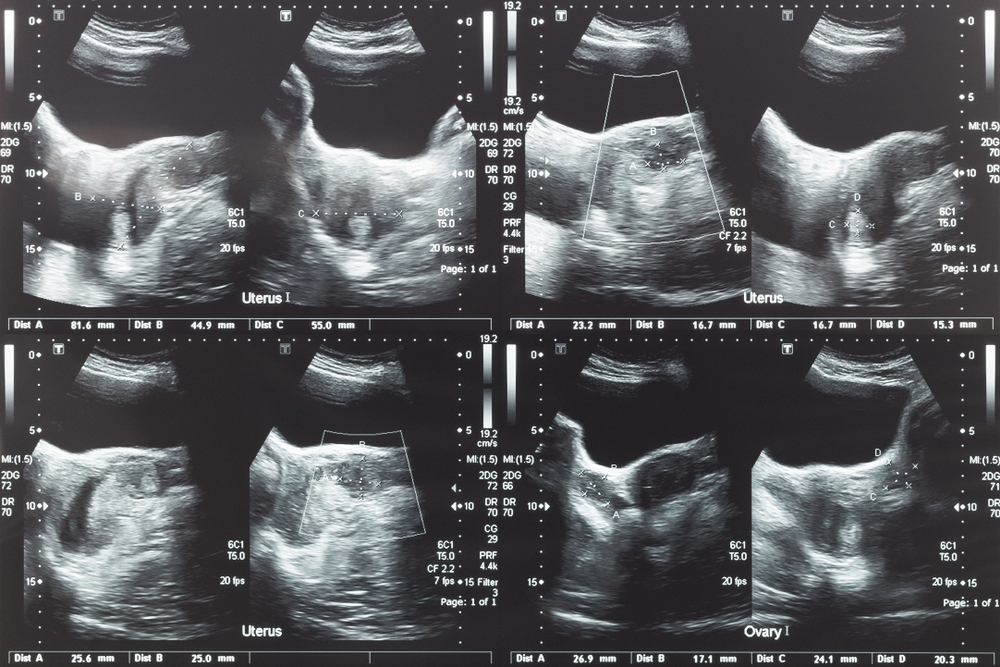

Doctor showing uterus and ovaries ultrasound scan

Before treatment, patients undergo a detailed evaluation to confirm fibroids as the cause of symptoms. Imaging studies, such as ultrasound or MRI, are used to assess fibroid size, location, and blood supply. This step ensures that UFE is both safe and effective for each individual case.